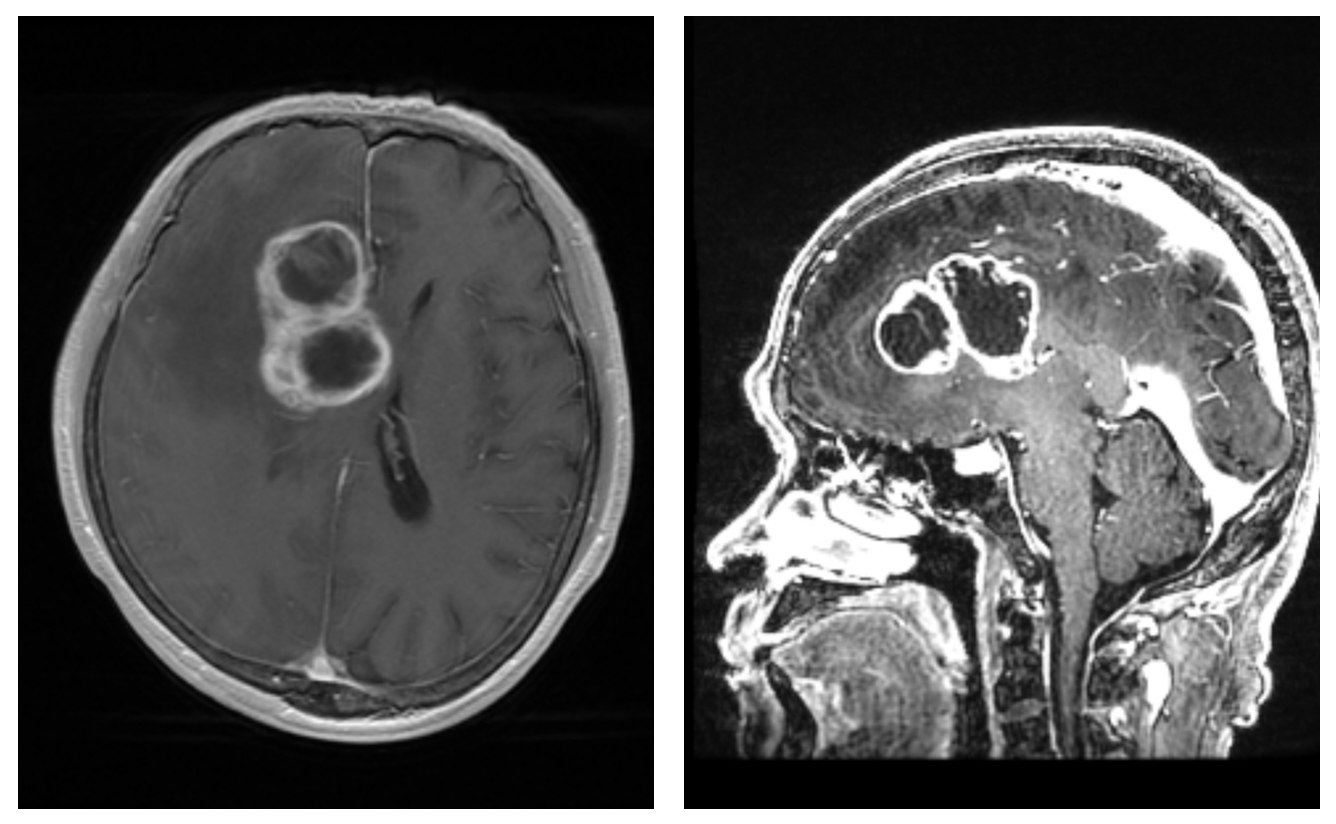

多发胶质瘤该如何处理_胶质瘤 - 好大夫在线

颞叶内侧恶性胶质瘤